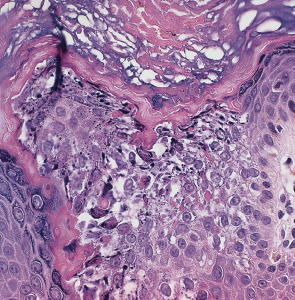

Pathology

Highly characteristic structural and ultrastructural abnormalities described as “epidermolytic hyperkeratosis” allow EI to be distinguished from other congenital ichthyoses. Key features on routine histologic examination are dense orthokeratotic hyperkeratosis, prominent acanthosis, hypergranulosis, and cytolysis of the suprabasal and granular layers leading to small intraepidermal blisters ( Fig. 57.7 ). Keratinocytes exhibit marked intracellular vacuolization and dense clumps of keratin intermediate filaments (KIFs). A mild perivascular lymphohistiocytic infiltrate is usually present in the upper dermis. Ultrastructural analysis reveals fragmented, clumped KIFs in the lower epidermis and perinuclear KIF shells in the upper epidermis.